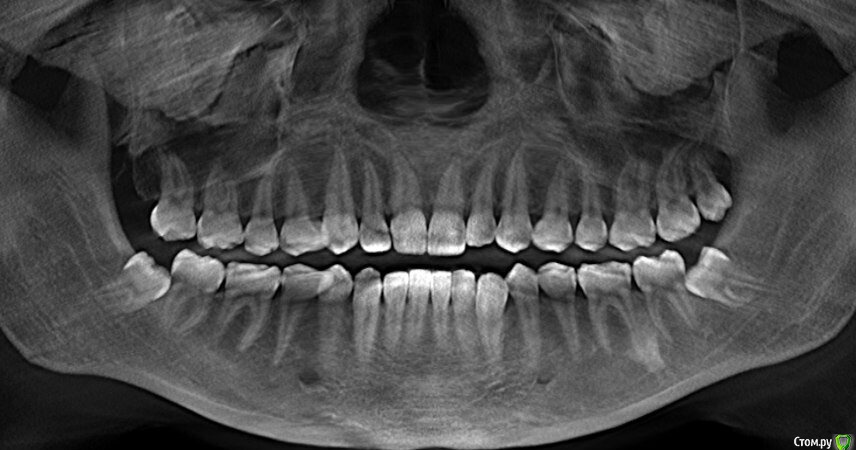

juliavesna Опубликовано 11 июля, 2017 Поделиться Опубликовано 11 июля, 2017 Добрый день! Буду благодарна, если кто-либо поможет мне разобраться с проблемой. Планировала начать ортодонтическое лечение. Сделала снимок 3D, где было выявлены 3 восьмерки (так как на прикрепленном снимке). Сейчас нахожусь на этапе удаления 2-й нижней восьмерки. Но также были выявлены пробемы с суставами (тяжело закрыть рот после максимального открытия, ощущение перескакивания, при чем в большей степени в 1 суставе). При том эти проблемы как бы непостоянны: иногда практически ничего не беспокоит, иногда периоды обострения. Также есть признаки стираемости. Большинство врачей настаивают на бруксизме. Была на консультации у нескольких врачей. Ортодонт направила на специалиста, который занимается заболеваниями внчс, которая на первой же консультации активно советовала сделать твердую шину. Меня, во-первых, смущает то, что врач не назначила никаких дополнительных обследований, снимков и т.д., только посмотрела мануально. Меня интересует возможность ортодонтического лечение в данной ситуации. Какие дополнительные обследования, снимки необходимо сделать? Нижний ряд довольно сильно скручен, зубы мудрости это еще больше ситуацию усугубили, верхние передние тоже повернуты в разные стороны, поэтому в ближайшем будущем очень хотелось бы исправить. Заранее спасибо. Ссылка на комментарий

juliavesna Опубликовано 11 июля, 2017 Автор Поделиться Опубликовано 11 июля, 2017 Вообще все ортодонты, к которым я обращалась, говорят о том, что с прикусом значинельных отклонений нет и сам по себе прикус и не может являться причиной проблем с внчс и т.д. Но при самостоятельном рассмотрении снимка я обратила внимание на то, что у меня зубы верхней челюсти не соответствуют одноименным зубам на нижней. Является ли это нормой? Ссылка на комментарий

juliavesna Опубликовано 23 сентября, 2017 Автор Поделиться Опубликовано 23 сентября, 2017 Дорогие доктора!Снова пишу вам крик о помощи! Прикрепляю все, что есть и смогла сделать! Если нужно что-то еще - сделаю! Снимок после удаления нижних зубов мудрости. Консультации у врачей привели к следующим итогам. 1 вариант лечения - ношение мягкой капы около 3 месяцев, затем ношение жесткой капы до полугода, затем ортодонтическое лечение.2 вариант - сразу ортодонтическое лечение. (Только 1 врач из всех посещенных предложил такое лечение). Врач считает, что все мои проблемы с суставами вызваны неправильным суженным прикусом и положением зубов. Остальные ортодонты не брались за меня. По первому варианту я решила не тянуть и уже мне сделали мягкую капу, но проблема в том, что я не могу ее долго носить, на ночь не рискнула пока, так как она давит на мои кривые передние зубы и они начинают болеть. Еще раз пишу, что состояние суставов стало таким в течение последних полутора лет. Раньше таких конкретных проблем не было. Буду благодарна любым советам и комментариям. Ссылка на комментарий